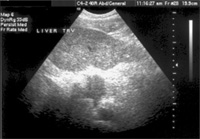

AFP and Ultrasound

That’s why doctors recommend that people at high risk of liver cancer also have an ultrasound examination every 6 to 12 months.